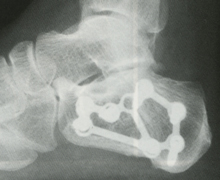

そこでは「かかとの剥離骨折(はくりこっせつ)」と診断され、直ぐに手術をすると治りも早いと言われたそうです。 その時の画像 赤丸の中がうっすらと剥がれているような状態に見える お母さんは今のこのに手術が必要なのか疑問に思い別の病院へ踵骨骨折は、骨折が後距踵関節面に及ばないもの(関節外骨折)と骨折が 後距踵関節面に及ぶもの(関節内骨折)とに大別されます。 《治療》 徒手整復は折れてずれた骨片を、できるだけずれのない状態に戻します。

かかとの骨の骨折です! かかとに繰り返し外力が加わることで起こるのが疲労骨折。骨粗しょう症があったり、靴底の不適合、オーバーワークだったりの背景があります。 高所からの飛び降りによる骨折もあります。 この場合の骨折は「圧迫骨折」である場合がほとんどです。7/2/16 疲労骨折 かかとの疲労骨折は、スポーツ選手や高齢者にみられるトラブルです。 スポーツ選手の場合、かかとの骨が上からほぼ垂直なラインで損傷し、 高齢者の場合は骨粗鬆症が原因 でかかとの骨が上から斜めのラインに亀裂が入ると言われています。26/5/ 骨折時の手術で埋め込んだボルトとプレートは抜く? 抜かない? 抜いた経験者からのアドバイス 年5月26日 年6月16日 3分